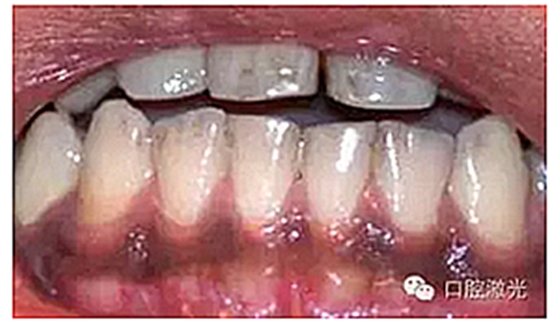

患者22岁,女性,主诉牙龈发黑。口腔检查显示牙龈部位呈黑色,但软组织健康,没有表皮粗糙或水肿现象。计划使用半导体激光进行治疗。手术前患者无需表麻或局麻。采用光纤接触方式,激光功率设定为1.5W至2W,连续模式。气化黑色牙龈区域上皮组织。不断重复该过程,直至足够深度的牙龈软组织表皮被去除干净。患者术后需采用漱口水进行口腔护理。

术前